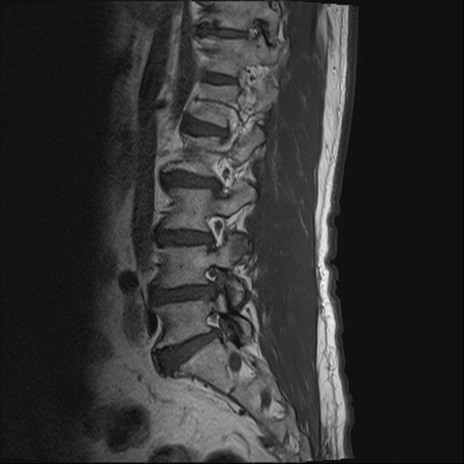

【整形】TIPS症例2 腰椎MRI T1WI(矢状断像)

【症例】70歳代男性

【主訴】左下肢痛

【現病歴】2週間前くらいから腰痛、左下肢痛あり。左臀部から大腿、下腿外側のしびれが常時ある。歩行とともに同部位の痛みあり。

【身体所見】Lasegue70-/60+、Bragard-/±、PTR ±/±、ATR -/-、IP 5/5、TA 5/4、TS 5/5、EHL 右第1足趾なし/3、FHL 5/5、hypersthesia(-)、足背動脈触知良好

異常所見と診断は?